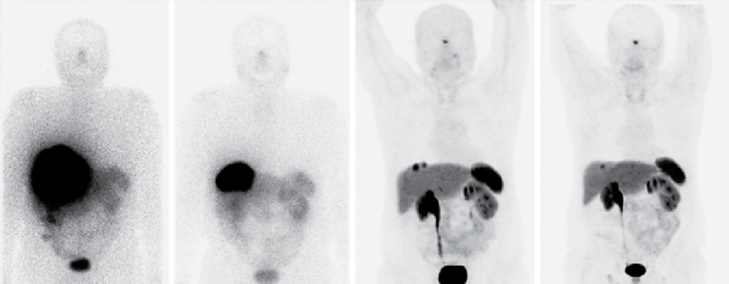

Lutetium-177 DOTATATE (abbreviated as 177Lu-DOTATATE therapy) is a form of radionuclide therapy targeting somatostatin receptors. Currently this treatment is being used in patients with neuroendocrine cancers (also known as carcionoid), pheochromocytoma, paraganglioma, meningioma and few other cancers.

A small quantity of DOTATATE (somatostatin receptor targeting agent) molecule is attached to radioactive Lutetium-177. The DOTATATE targeting molecule when injected intravenously targets the radiation of 177Lu to the cancer target sites. The delivered radiation then kills the cancer cells.

177Lu-DOTATATE therapy is currently used in patients with metastatic neuroendocrine cancer (aka carcinoid cancer) and few other cancers such as pheochromocytoma, paraganglioma and meningioma.